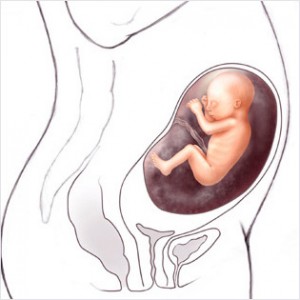

Bu haftadan itibaren artık bebek rahim içerisinde oldukça fazla yer kaplar ve bu yüzden ona hareket edecek fazla alan kalmaz. Eğer bebeğinizin hareketlerinde azalma his ederseniz endişe etmeyin, hareketlerin azalması bu yüzdendir.

Bebeğin Boyutu: 43.7 cm, 1.9 kg